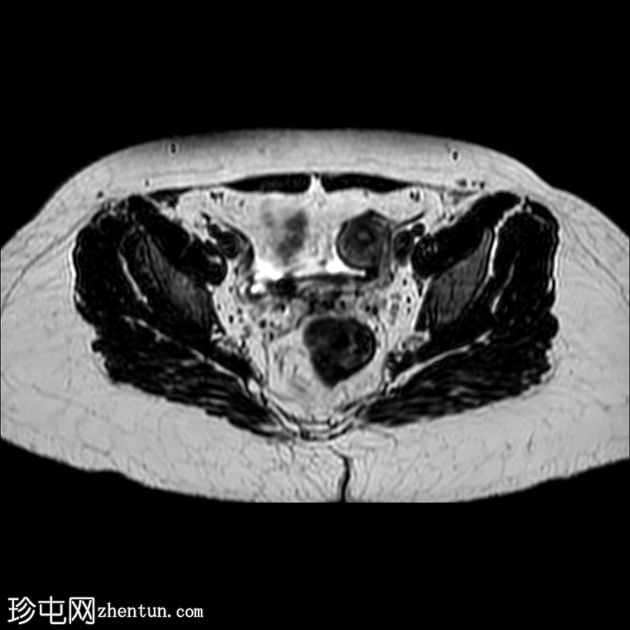

轴位

T1加权像

T2加权像

盆腔两侧可见两个残角,位于双侧卵巢尾侧。可见一条水平带连接两个残角。左侧残角呈腔状,右侧残角呈非腔状。

可见宫颈阴道发育不全,从两个残角延伸出少量发育不良的宫颈组织带。

双侧卵巢功能正常,可见卵泡。

本病例展示了一种 Mayer-Rokitansky-Küster-Hauser 综合征 (MRKH),其特征为子宫缺失和双侧残角;左侧子宫角呈腔状,右侧子宫角呈非腔状。子宫角位于盆腔两侧,双侧卵巢尾侧,并由一条水平带连接。该病伴有宫颈阴道发育不全。